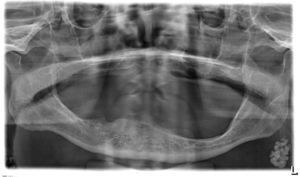

Hay que hacer el diagnóstico diferencial con una sialolitiasis de la glándula parótida que, sin embargo, es un cuadro muy infrecuente. Las calcificaciones ganglionares suelen manifestarse en la zona caudal de los ángulos mandibulares y se asocian en general a enfermedades totalmente diferentes como sarcoidosis, tuberculosis o también enfermedades oncológicas (fig. 2).